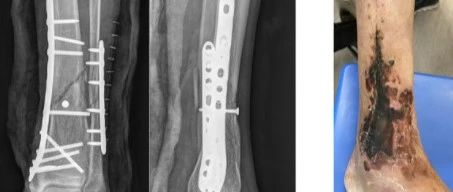

骨科保护软组织不可忽视的9点

一个坏的软组织可能是由多种因素导致的高能量损伤,不适当的切口,不合适的手术时机,不恰当的术中操作,不精细的缝合技术,不防止引流,没有放置VSD,等等等……最终导致皮肤坏死,内固定外露,伤口迁延不愈。骨折几乎总是与某种程度的软组织损伤有关。虽然外科医生无法改变初始损伤造成的损伤程度,但他们可以通过熟练使用器械和牵开器,避免对这些受创组织造成进一步损伤。相反,在寻求实现骨折的解剖修复时,外科医生往往忽视了骨折广泛暴露造成的...